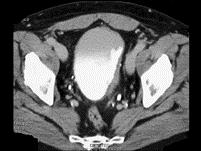

问题 男,55岁,血尿半月余,请根据其影像,判断其最可能的诊断 ( )

选项 A、膀胱憩室伴感染 B、慢性膀胱炎 C、膀胱癌 D、膀胱憩室 E、膀胱结石

答案 C